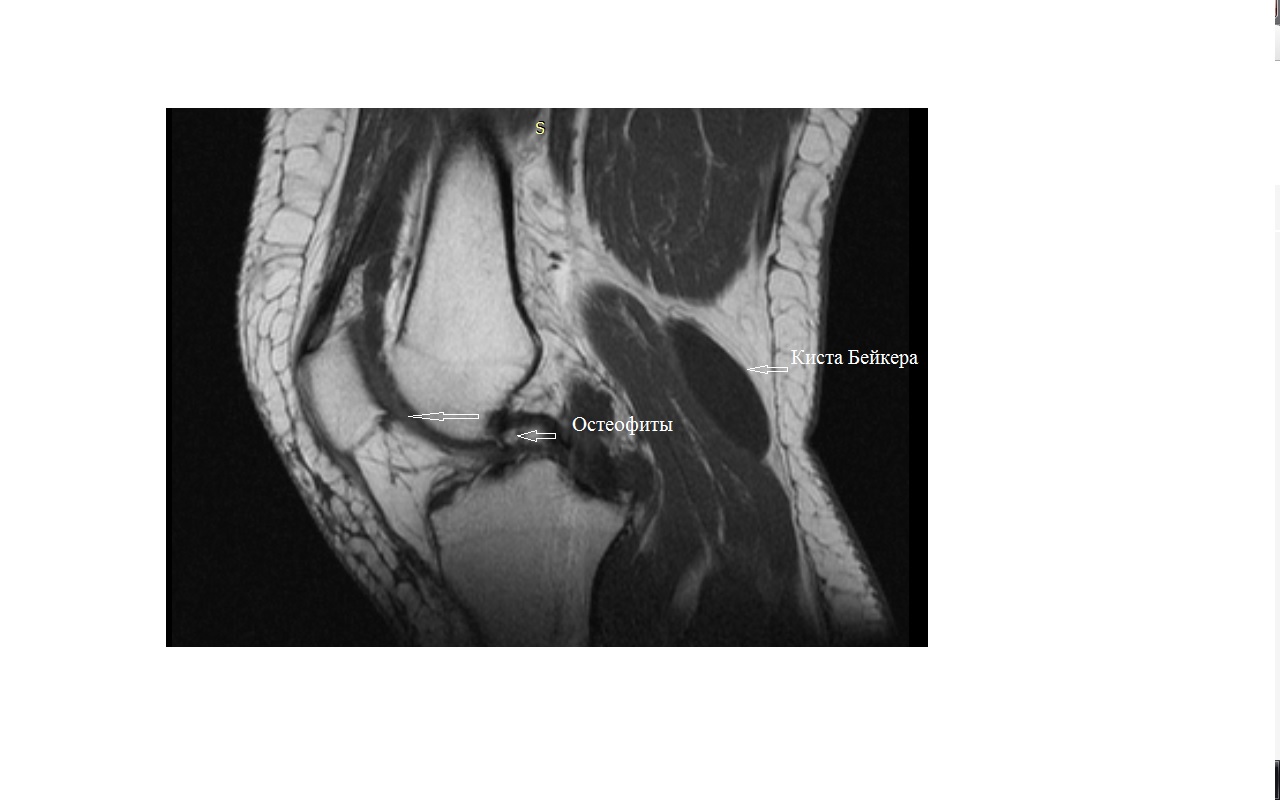

Фото и диагностика кисты Бейкера